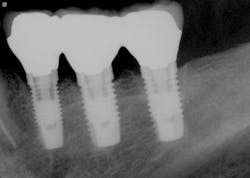

The most critical aspect of any implant system is the interface between the implant fixture and its surrounding bone (figures 1-5). Integration between the fixture and its surrounding bone is the foundation of modern implant dentistry. There is little we can do to modulate bone healing, but we can modify the implant fixture itself.

Figures 1-5: Figures 1 through 4 illustrate, respectively, a seven-year follow-up visit and a three-year follow-up visit of two different implant systems. Implant No. 22 (figure 5) shows peri-implant radiolucency following functional loading, indicating fibroencapsulation and loss of integration into bone, necessitating removal.